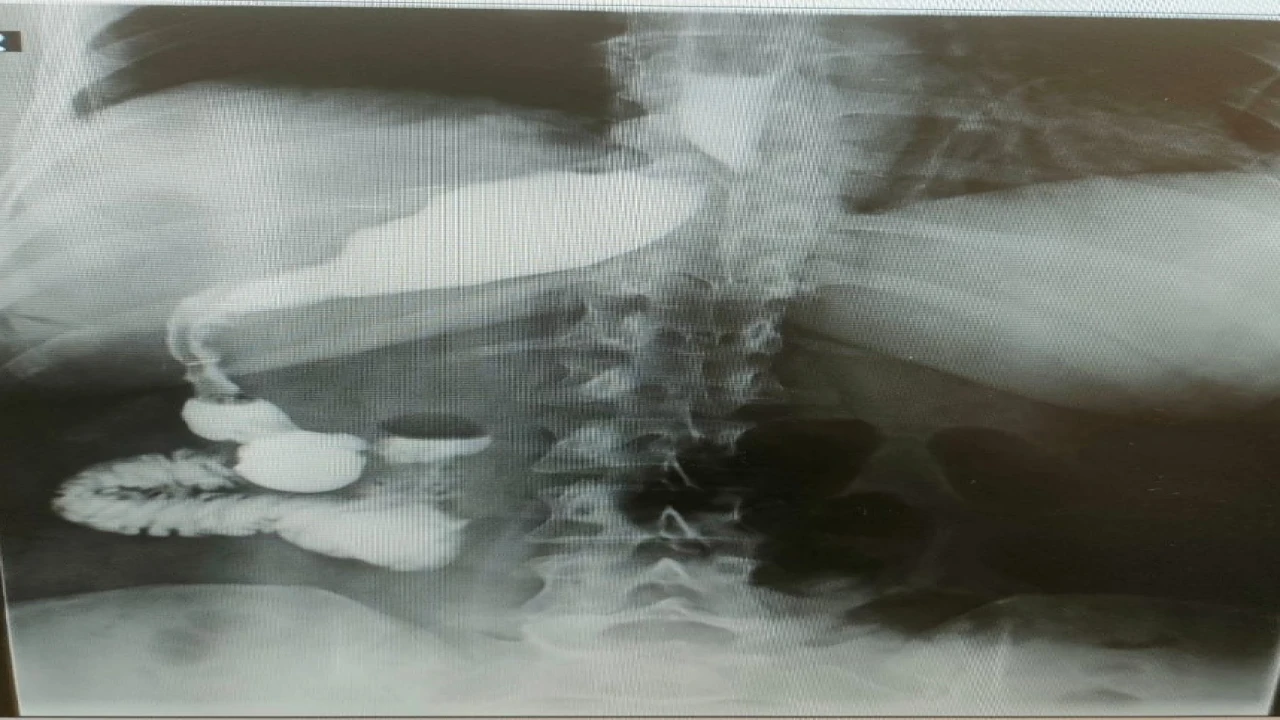

Almanya’da hemşire olarak görev yapan Antje Kirscht, tüp mide ameliyatı olmak için sosyal medyada yaptığı araştırmalar sonucunda Memorial Antalya Hastanesi Genel Cerrahi Bölüm Başkanı Prof. Dr. Alihan Gürkan’a ulaştı. İlk kez Antalya’ya gelen 46 yaşındaki Kirscht, 110 kilo ağırlığıyla obezite tedavisi için başvurdu. Almanya’da kendisine organlarının ters olabileceği yönünde bir tanı konduğunu ifade eden Kirscht, bu bilginin ameliyat sırasında ne anlama geldiğini öğrendi. Ameliyat esnasında cerrahi ekip, Kirscht’in midesini karaciğerinin arkasında, sağ tarafta buldu. Bu sıra dışı anatomik durum, hem hasta hem de ekibin şaşkınlık yaşamasına neden oldu.

Ameliyatı gerçekleştiren Memorial Antalya Hastanesi Genel Cerrahi Bölüm Başkanı Prof. Dr. Alihan Gürkan, yaşadıkları şaşkınlığı şu sözlerle dile getirdi: “Çok yapılan bu operasyonlar içerisinde hastanın değişik bir anomalisi vardı. 100 binde bir görüldüğü söyleniyor. Organların hepsi ters olabiliyor. Bu daha sık görülen bir şey ama bu hastada bütün organlar yerli yerinde ama sadece mide sağ tarafa kaymış. Yani karaciğerin arkasına gitmiş. Operasyona başladığımızda mideyi bulamadık. Karaciğeri kaldırınca mideyi sağ tarafta gördük. Bu çok nadir bir durum. 2023 yılı verilerine göre, böyle bir tüp mide ameliyatı dünyada yalnızca 50 kişiye uygulanmış. Biz de bu vakayı başarıyla gerçekleştirdik. Teknik açıdan bizi zorlayan ancak deneyimimizi artıran bir ameliyat oldu”.

Prof. Dr. Gürkan, ameliyatın detaylarına değinerek, “Tüp mide operasyonunun ayna görüntüsünü yaptık. Normalde sol tarafta yaptığımız obezite ameliyatını bu hastada sağ tarafta gerçekleştirdik. Midenin karaciğerin arkasında olması ameliyat süresini 15 dakika uzattı ve toplamda 1 saat sürdü. Bizim için de hoş bir tesadüf oldu” diye konuştu.